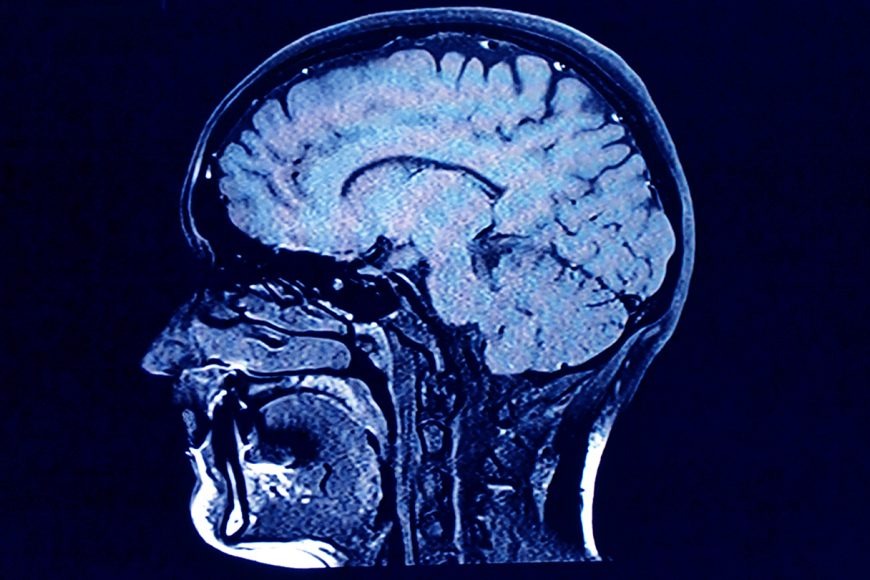

కరోనా వైరస్ మరిన్ని సమస్యలకు దారితీస్తున్నట్టు శాస్త్రవేత్తలు వెల్లడించారు. ఇప్పటి వరకు ఇది ఊపరితిత్తులకు మాత్రమే హాని చేయగా, ఇప్పుడిది గుండె, మూత్రపిండాలను కూడా దెబ్బతీస్తోందని, చర్మంపై దద్దుర్లు, రక్తస్రావ సమస్యలు కూడా తలెత్తుతున్నట్టు శాస్త్రవేత్తలు గుర్తించారు. కరోనా ఉద్ధృతి కారణంగా పక్షవాతం, మెదడులోని ఇన్ఫ్లమేషన్, కండరాల రుగ్మతలకు సంబంధించిన కేసులు పెరిగే అవకాశం ఉందని అధ్యయనాలు పేర్కొన్నాయి.

కరోనా రోగుల్లో న్యూరో సైకియాట్రిక్ లక్షణాలు అరుదేమీ కాదని పేర్కొన్నారు. కుంగుబాటు, ఆదుర్దా వంటి మానసిక సమస్యలు 25 శాతం మంది రోగుల్లో కనిపిస్తున్నట్టు పేర్కొన్నారు. మెదడుకు సంబంధించిన తీవ్రమైన రుగ్మతలు మాత్రం చాలా అరుదుగానే కనిపించినట్టు శాస్త్రవేత్తలు తెలిపారు. అయితే, నాడీ సమస్యలు మాత్రం బాధితులకు కొన్నేళ్లలో భారంగా మారే అవకాశం ఉందని పేర్కొన్నారు.